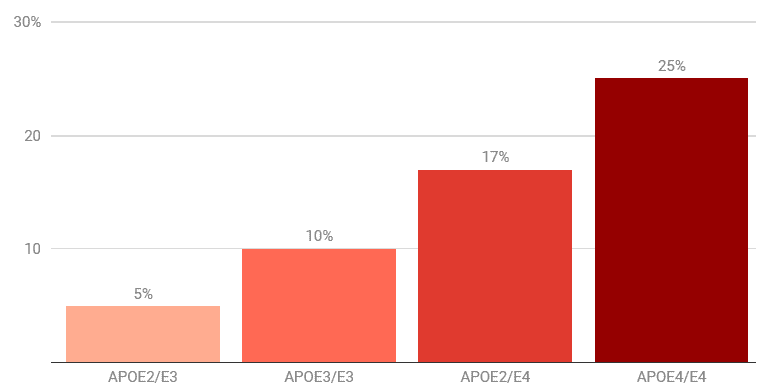

لا أحد يعرف سبب مرض الزهايمر على وجه اليقين. لكن إحدى الحقائق عن المرض وصلت إلى حالة لا تقبل الجدل تقريباً. فاستناداً إلى نمط الجين المسمّى APOE الذي يرثه الشخص، يمكن أن يكون خطر إصابته بهذا الاضطراب الدماغي نصف المعدّل الوسطي، أو أكثر منه بـ 12 مرة.

ويمتلك جين APOE (الذي يسمى في بعض الأحيان "جين النسيان") ثلاثة أنماط شائعة تسمّى 2 و3 و4. إذ يقلل النمط 2 من خطر إصابة الشخص ويكون النمط 3 عند المعدّل الوسطي، بينما يزيد النمط 4 من احتمال الإصابة بشكل كبير. ويعدّ الخطر كبيراً للغاية لدرجة أن الأطباء يتجنبون اختبار الأشخاص للكشف عن نمط الجين APOE لأن النتيجة السيئة يمكن أن تكون مزعجة، وليس هناك ما يمكن فعله حيال ذلك. فلا يوجد علاج، ولا يمكنك تغيير جيناتك أيضاً.

خطر الإصابة بمرض الزهايمر في سنّ الثمانين، حسب النمط الجيني

البيانات مأخوذة من نساء بيض لديهن قريب واحد مصاب بالمرض. يرث كل شخص نسختين من الجين ApoE.

لا تزال وظيفة الجين غير مفهومة تماماً (له دور في نقل الكوليسترول والدهون)، لكن كونه عاملاً خطراً ما زال مخيفاً. ووفقاً لجمعية الزهايمر، فإن حوالي 65٪ من المصابين بالزهايمر لديهم نسخة واحدة على الأقل من الجين الخطِر. أما بالنسبة للأشخاص الذين تكون لديهم نسختان خطرتان من الجين (واحدة من الأب وواحدة من الأم)، فإن الخرف يصبح مؤكداً تقريباً إذا ظلوا على قيد الحياة لمدة كافية للإصابة بالمرض.

ومع ذلك، فإن بعض الناس يرثون نسخة من النمط 4 ونسخة من النمط 2، وهي النسخة الأقل خطراً من هذا الجين. يكون خطر إصابة هؤلاء الأفراد أقرب إلى المعدل الوسطي، مما يشير إلى أن النسخة الحامية من الجين تعاكس النسخة الخطرة.